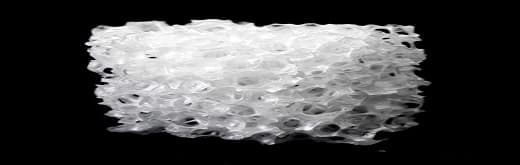

Applications wise it has emerged integral to orthopedic, dental, biomedical, cardio-vascular solutions, among others. In applications pertaining to orthopedic many kinds of bioceramics are employed and the choice of bioceramics is governed by the kind of defects that it rectifies. Further, the employment of nanoscale bioceramics to fabricate various usable products has revolutionized the manner in which bioceramics have been used in orthopedic surgery due to the widely acknowledged effectiveness of nanomaterials in osseointegration and osseoconduction as well as its capability to provide a porous network of precise nature that is determinant of bone repair rate.

To this end its important to note that the chemicals and materials industry has made significant strides and has witnessed prolific engagement in research and development activities bringing about a sea change in the capabilities of bioceramics. For instance, in March 2018, Dimension Inx, which is a biofabrication company that leverages the capabilities of patented 3D-printing biomaterials design and the platform to manufacture had reportedly commercialized a regenerative medical product that has fundamentally changed the way human diseases and debilitation have been treated thus far, called Hyperelastic Bone™. It is composed of less than 90 wt.% hydroxyapatite, which is the same mineral found in bones and teeth. The unique aspect that makes it a path-breaking product innovation in the bioceramics market is that despite being mostly mineral it retains flexibility and can be printed at room temperature, which either can be shaped generically or printed to the specifics matching with a particular patient. As of March 2020, the issuance of U.S. Patent No. 10,584,254, was reportedly announced by the company that covers its proprietary biomaterials design and 3d-printing manufacturing system.